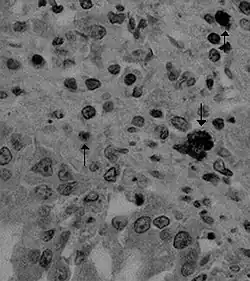

| Canine coronavirus antigen (arrows) in canine lung tissue | |